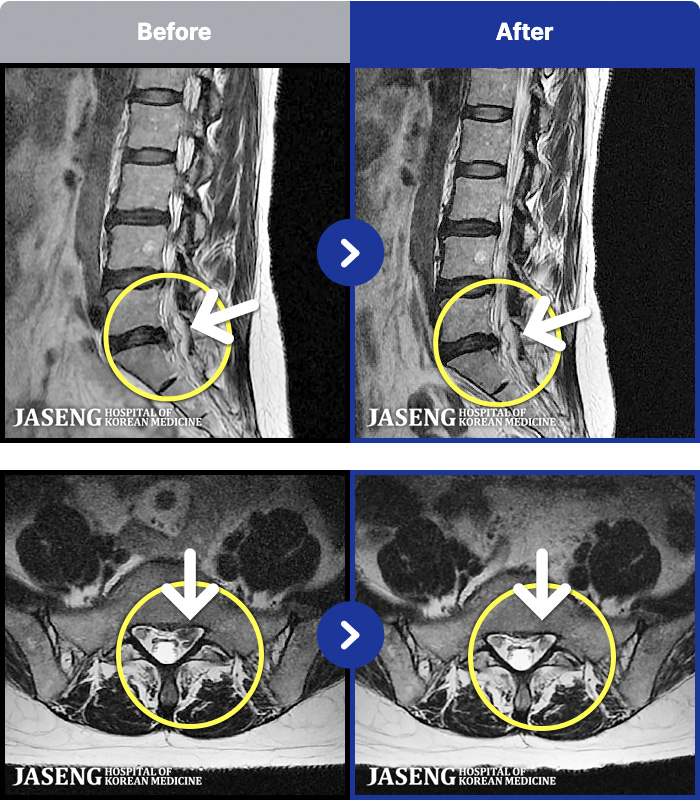

[ϻ] 24.07.25~25.08.01

ȯںп Ǹ ǿ ԿǾ, ο ġ ۿ Ƿ ġḦ Ͻñ ٶϴ.